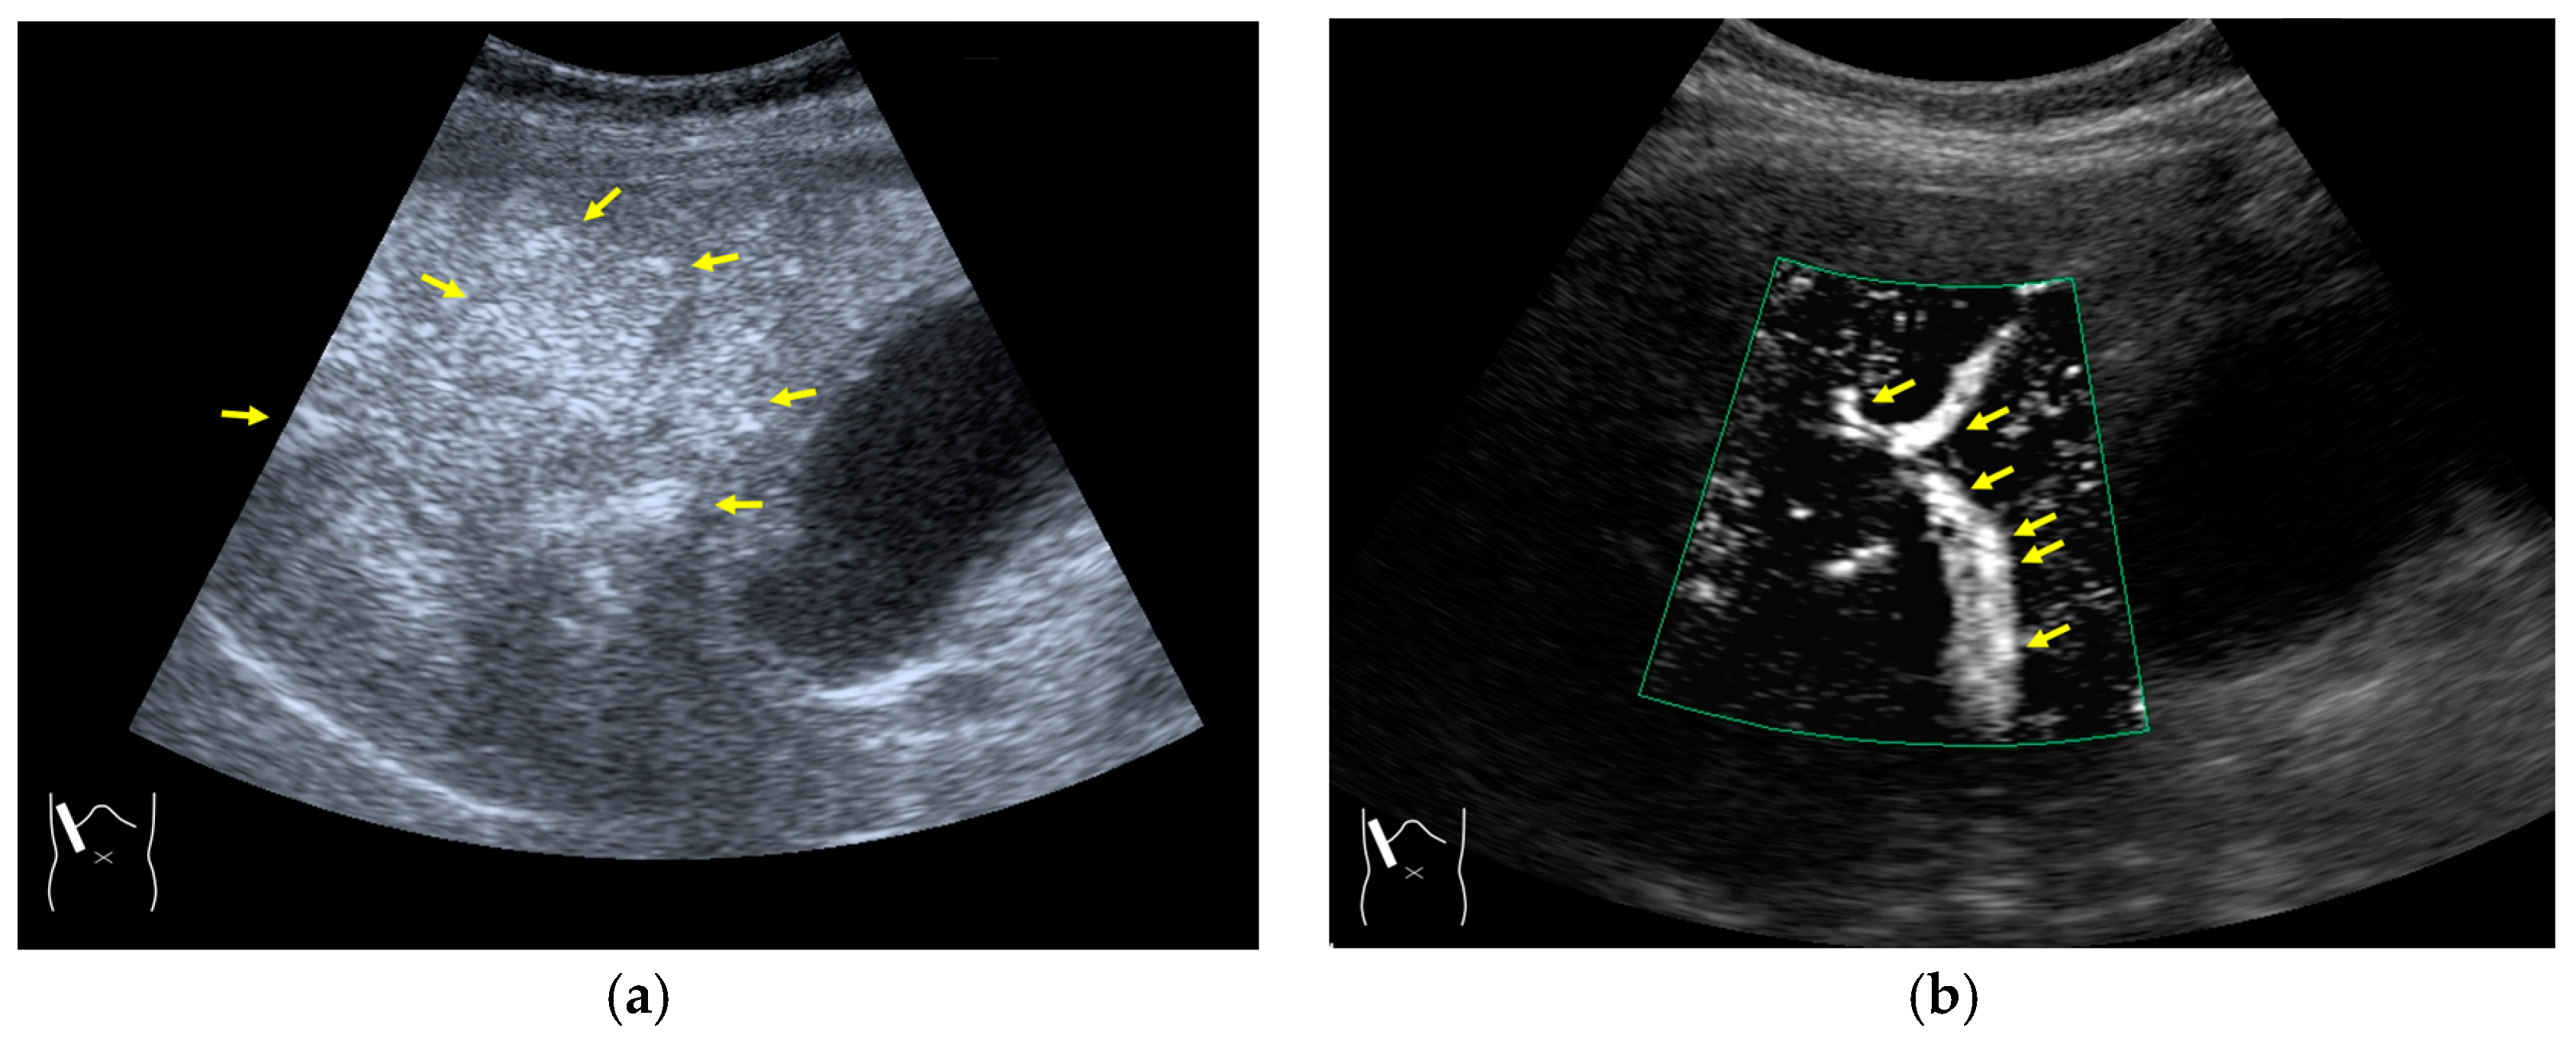

Current US machines reconstruct B-mode US images based on the assumption that sound passes through all parts of human tissues in a straight line and at a constant acoustic velocity (1540 m/s), and this assumption is applied to all scanning planes. The displayed position in a US image usually corresponds with the actual position on the structure. Strictly speaking, however, the acoustic velocity changes according to the tissues [44,45]. Thus, when a plane containing tissues with different acoustic velocities is scanned, sound refraction occurs at the interface between these tissues according to Snell’s law. As a result, the displayed position of point A (the true location) along the line that passes through the interface is falsely displayed at point A’ (a different position) in the B-mode US image as if there was no sound refraction. This refraction artifact is clearly seen in a cirrhotic liver (Figure 3), around a round mass (e.g., a hepatic cyst) (Figure 4) and below the rectus muscles in the transverse scanning plane of the upper abdomen (Figure 5). We will now provide a brief explanation for these three artifacts (Figure 3, Figure 4 and Figure 5). In macronodular liver cirrhosis, sound refraction occurs at the irregular hepatic surface, resulting in the improper positioning and display of echo brightness in the US image [44,45,46], giving the appearance of a “tricolor flag” [46] (Figure 3). When a US beam passes through a mass with an acoustic velocity different from that of the surrounding hepatic parenchyma, it changes direction twice due to sound refraction, first at the liver parenchyma–mass lesion entrance interface and again at the mass lesion–liver parenchyma exit interface. The liver structure behind the mass lesion thus appears to be deformed in B-mode US and heterogeneous in CEUS (Figure 4). As has been reported, sound refraction occurs most clearly at both edges of a mass lesion, and the degree of sound refraction is nearly proportional to the incidental angle of the US beam striking the liver parenchyma–mass lesion interface. Globally speaking, the degree of sound refraction is accentuated as the US beam strikes peripheral to the mass lesion. This is why the posterior echo behind the mass lesion is not homogeneous, as observed in Figure 4. In the transverse scanning of the upper abdomen, the US beam is largely refracted, first at the anterior wall of the rectus muscles and then at the posterior wall of the muscle (Figure 5c). As a result, the liver below the rectus muscles is more or less deformed in B-mode US and CEUS, as seen in Figure 5a,b. The most useful prevention strategy is to use the reference B-mode image (the so-called dual-image technique), which allows for a simultaneous comparison between the CEUS and B-mode images.

Figure 3.

Refraction artifact (1): many vertical bands of different echogenecities in macronodular cirrhosis. (a) Gray-scale US reveals that the left hepatic lobe is markedly deformed with an irregular surface. The liver gives the appearance of a tricolor flag. (b) CEUS shows the liver to be composed of many vertical bands of different brightness (arrows), giving the appearance of a tricolor flag.

Figure 5.

Refraction artifact (3): hypoenhanced lines due to US refraction. (a) CEUS shows many hypoechoic lines throughout the liver parenchyma via transverse scanning (arrowheads). (b) The liver’s left lobe shows none of the lines seen in (a) via sagittal scanning. (c) A schematic drawing of sound refraction due to rectus abdominus via transverse scanning plane. The US beam changes direction twice, first at the surrounding tissue–rectus muscle interface, then at the rectus muscle–surrounding tissue interface.